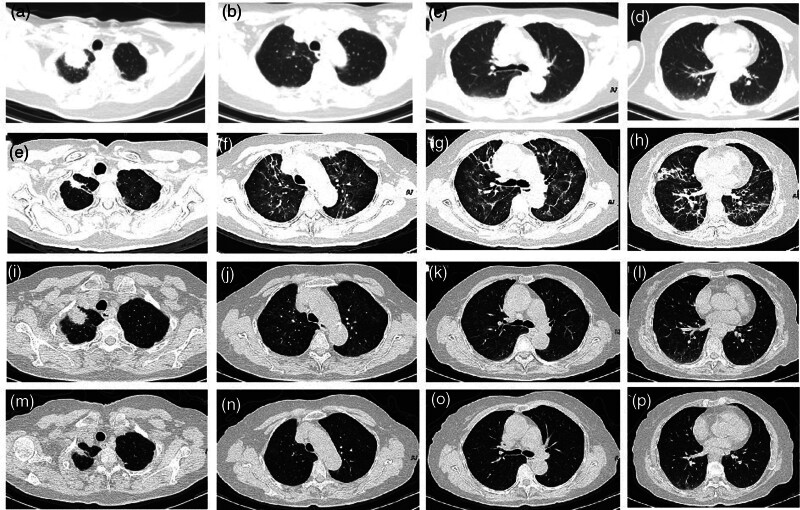

Almonertinib, a representative epidermal growth factor receptor tyrosine kinase inhibitor (EGFR-TKI), is the first-line standard treatment for EGFR-mutant advanced non-small-cell lung cancer; however, it may induce drug-related interstitial lung disease (ILD). This case report presents a 67-year-old female with advanced lung adenocarcinoma, who was diagnosed with an EGFR exon 19 deletion mutation. After 2 months of first-line almonertinib treatment (110 mg/day), a PR was achieved; however, progressive respiratory distress emerged. Chest computed tomography revealed ground-glass opacities accompanied by grid-like changes in both lungs, leading to a diagnosis of EGFR-TKI-related ILD (grade 2). Following glucocorticoid treatment and medication discontinuation, the lung lesions improved. Given the persistent tumor activity, the patient was switched to firmonertinib (80 mg/day) for targeted therapy. This switch did not lead to a recurrence of ILD symptoms, with a progression-free survival exceeding 5 months and good tolerability. This suggests that for patients with ILD associated with almonertinib and firmonertinib may serve as an effective and safe alternative. Closely monitoring ILD in clinical practice and promptly switching to similar drugs may avoid chemotherapy intervention and optimize treatment strategies. This case marks the first report of clinical experience achieving sustained remission by switching to a similar drug, firmonertinib, in patients with ILD related to almonertinib.

Abstract Image